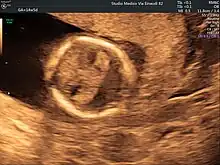

Ultrasound scan of a fetal head at 14 weeks of pregnancy with partial absence of the midline